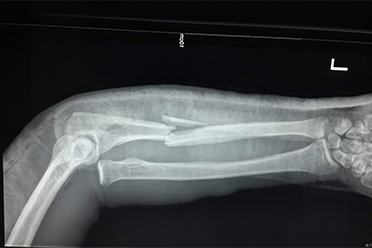

作为孩子家长当孩子受伤时首先要头脑保持冷静,需第一时间初步判断孩子是否发生了骨折与脱位。一般来讲,如果受伤肢体出现了剧烈疼痛、畸形、异常活动或活动受限,基本上可以判定孩子可能发生了骨折或者脱位。

当然,骨折的专有体征被定义为畸形、异常活动和骨擦音和骨擦感。但不建议孩子家长检查孩子受伤肢体有无骨擦音和骨擦感,因为这种检查如操作不当很可能加重骨折,造成二次伤害。